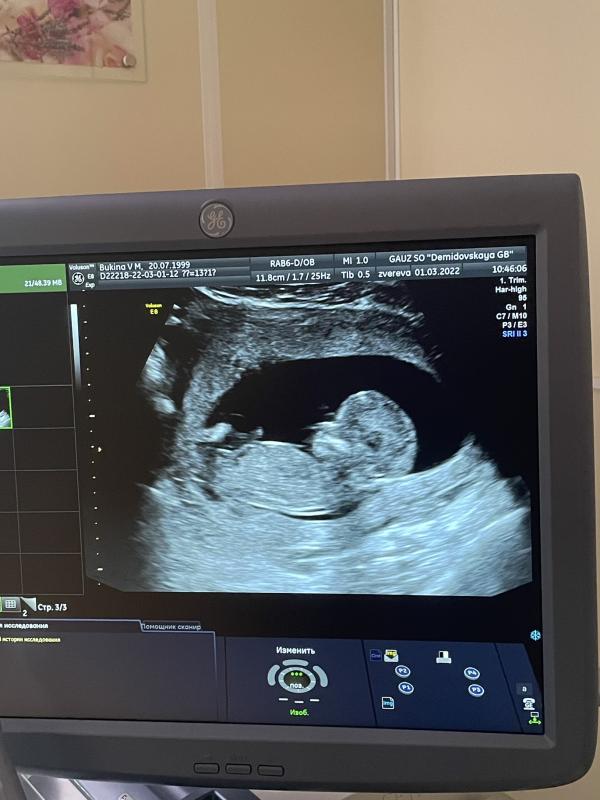

Первый скрининг🤰🏼

Я проходила его в перинатальном центре Нижнего Тагила и что меня в первую очередь удивило - очень милые и дружелюбные врачи. Везде, в регистратуре, в кабинетах, в коридоре, на узи. Почему удивило? Я слышала очень много отзывов, что там все настолько плохо и врачи общаются с тобой как не понятно с кем. Опровергаю, хотя не спорю что возможно мне просто попалась такая смена, но верю что и потом будет все хорошо!🙏🏼

Мне измерили давление, взяли кровь из вены, затем узи и консультаци...